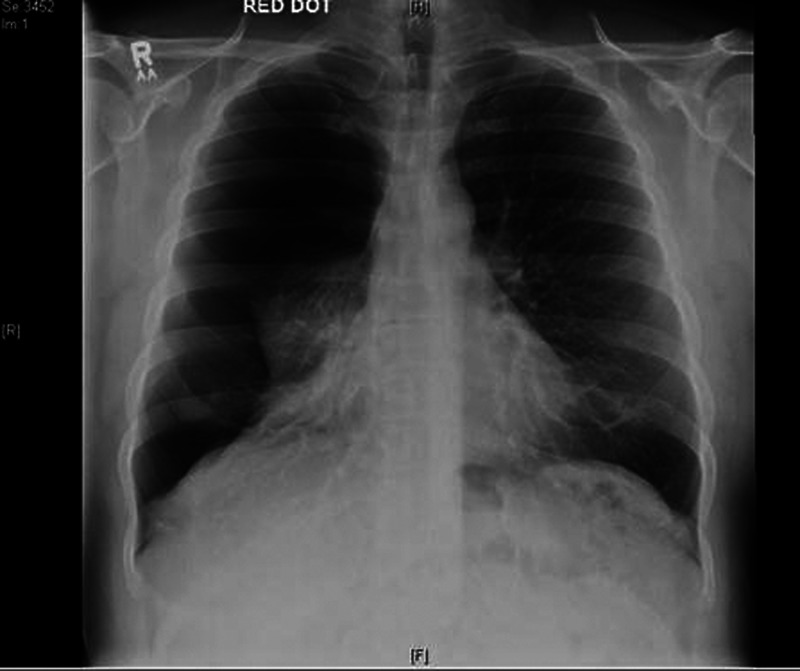

Chest radiograph revealed a large right-sided primary spontaneous pneumothorax (PSP) (figure 1), which was aspirated unsuccessfully. A chest drain was inserted with uneventful recovery (figure 2).

Figure 1.

Erect anteroposterior chest radiograph showing large right-sided pneumothorax with almost complete right lung collapse with loss of right lung markings. There is no tracheal deviation. Pneumothorax defined as ‘large’ by the presence of greater than 2 cm rim between lung margin and chest wall.1